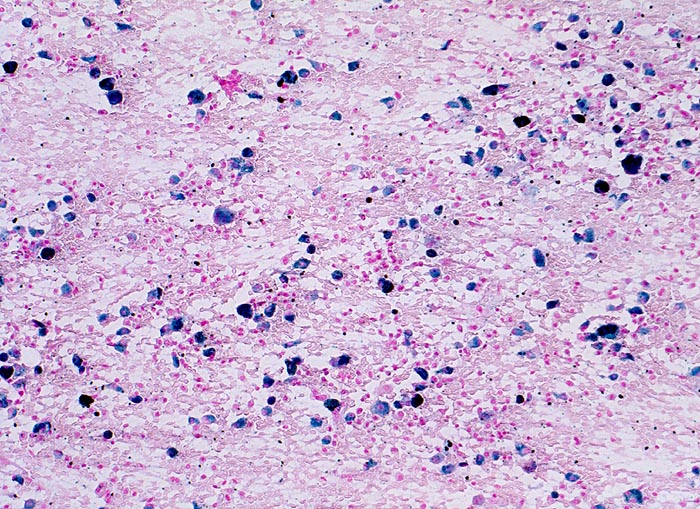

PathoPic ID 3382 - chronische Lungenstauung: Herzfehlerzellen

chronische Lungenstauung: Herzfehlerzellen

vaskulär / Durchblutungsstörung

Sputum

Lunge, Mediastinum mit Thymus

Im Sputumausstrich sind in der Eisenfärbung zahlreiche Makrophagen erkennbar, die eisenhaltiges Hämosiderin enthalten.

Patient mit koronarer Herzkrankheit und Linksherzinsuffizienz.

Zytologie

100